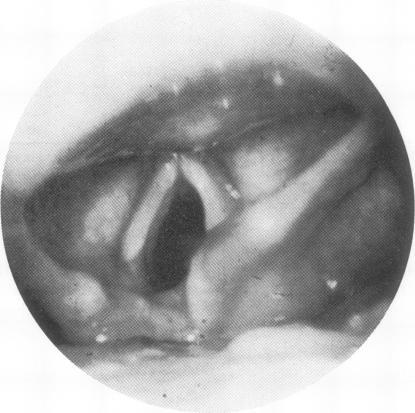

Airflow in unilateral vocal cord paralysis before and after Teflon injection.

The effect of unilateral vocal cord paralysis and intracordal Teflon injection on maximum expiratory and inspiratory flows was studied in 15 consecutive patients. Ten patients had a ratio of forced expiratory flow to forced inspiratory flow at 50% vital capacity (Ve50/Vi50) more than one. Of the remaining five, four had low Ve50 consistent with underlying bronchial disease. Repeat studies were obtained in 10 patients two or more weeks after Teflon injection into a vocal cord for voice therapy. Maximum expiratory flow rates did not change (means 6.64 +/- 0.881/sec before and 6.47 +/- 1.101/s after injection). Inspiratory flow at 50% vital capacity improved in all six patients with a forced expiratory volume in one second (FEV1) greater than 75% of the forced vital capacity (FVC). In patients with an FEV1 less than 75% FVC, no consistent changes could be seen. We conclude that a high Ve50/Vi50 suggestive of variable extrathoracic airways obstruction is a frequent finding in the presence of unilateral vocal cord paralysis. Teflon injection does not cause a significant reduction in forced expiratory flows and improves inspiratory flows in subjects without evidence of underlying bronchial disease.